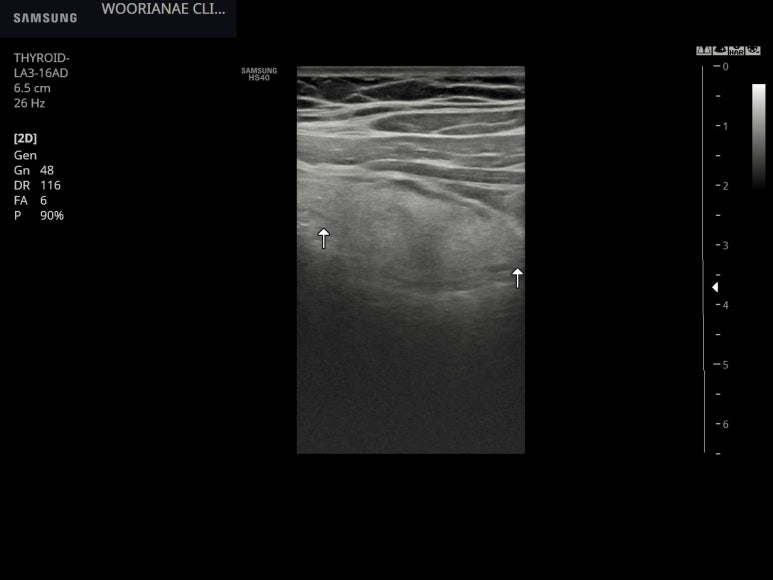

리니어 프로브로 아래와 같이 저음영 경계를 가지는 고음영 종괴로 관찰된다.

위아래 장경